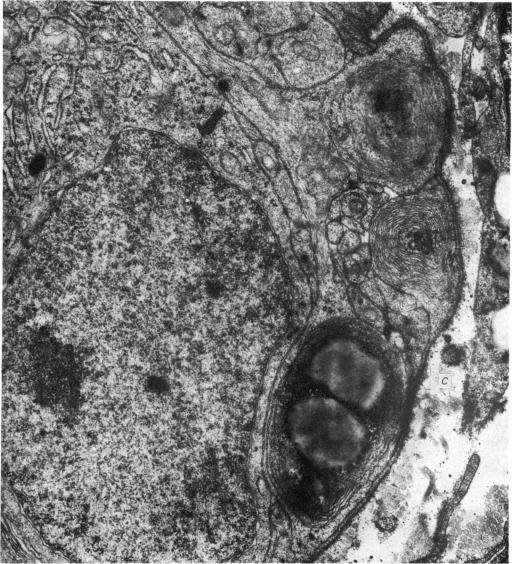

The pineal gland of chicks treated with oestrogens and androgens has been studied histochemically and ultrastructurally from post-hatching until 90 days of age. The results obtained may demonstrate a precocious maturity of the gland caused by its response to the early high level of sex hormones circulating in the blood.

对用雌激素和雄激素处理过的雏鸡的松果体进行了组织化学和超微结构研究,研究从雏鸡孵化后直至90日龄。所获得的结果可能表明,由于松果体对血液中早期高水平性激素的反应,该腺体出现早熟。